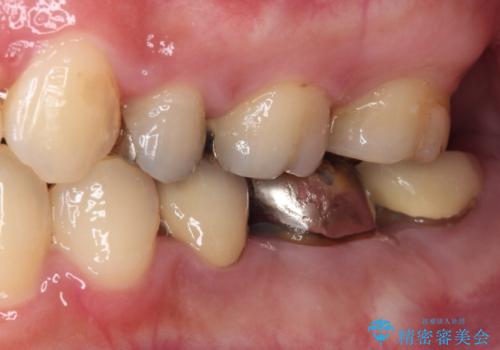

- 他院で抜歯矯正を終えた後、銀色の目立つ奥歯を白くしたいとのことで来院された患者様です。

既にセラミッククラウンが装着されている歯もありますが、不自然な色合いや黒い縁も気になるので、一斉に補綴治療をして統一感を持たせることとしました。